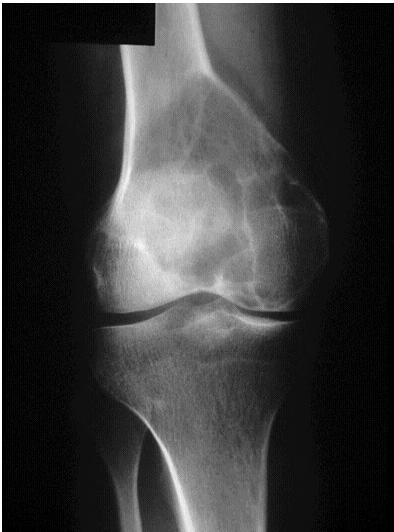

Non-ossifying Fibroma

site: Diaphyseal, metaphysal size: partial matrix: Mixed - Narrow zone of transition, well defined, syndosmosis soft tissue involvement: No tissue involvement